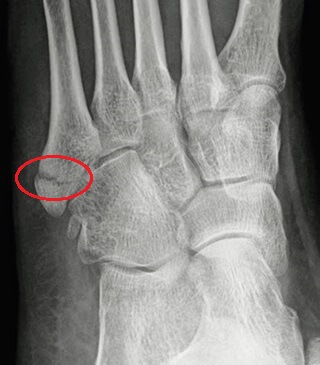

A Pseudo Jones fracture, aka avulsion fracture, is a common foot injury.

These fractures occur at the base of the fifth metatarsal, the long bone on the outer side of the foot.

A Pseudo Jones fracture is an avulsion fracture that occurs when a small piece of bone is pulled away from the base of the fifth metatarsal.

The fifth metatarsal is the long bone on the outer side of the foot that connects the mid-foot to the pinky toe.

At the base of the fifth metatarsal is an area known as the tuberosity, a bony prominence on the outside of the foot. The peroneus brevis tendon attaches directly to the tuberosity.

If the foot or ankle is suddenly forced inwards, it pulls on the peroneus brevis tendon. If the force is strong enough, the tendon is torn away from the tuberosity, pulling a small fragment of bone with it. This is known as an avulsion fracture foot or Pseudo Jones fracture.

Pseudo Jones avulsion fractures occur in the zone 1 region, at the proximal end of the metatarsal base.